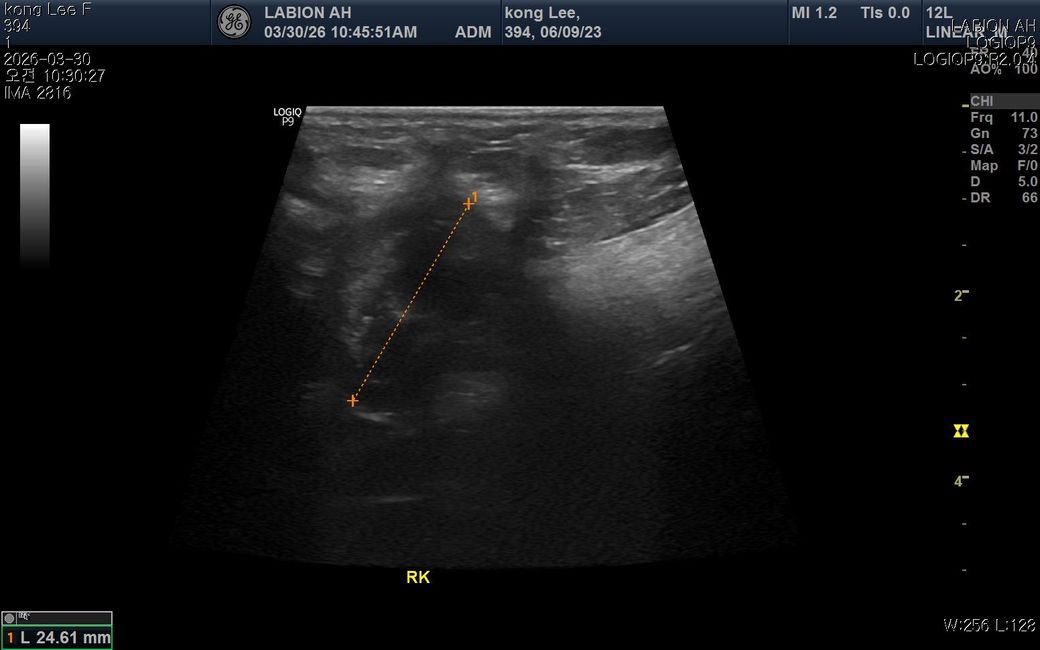

최근 황태 간식을 약 2~3개월 동안 매일 급여해왔고 염분이 느껴져 급여를 중단했습 니다. 이후 소변횟수가 살짝 감소하고 음수량이 평소보다 증가했고 동시에 밤잠이 줄고 낮에 무기력해졌습니다 원래 저녁에8시간정도 잤는데 중간에 한두번씩 깨거나 6시간으로 줄었고 밤잠이 줄어 낮에 좀 피곤해하는데 혹시 나트륨 섭취로 인해 체내 호르몬에 이상이 생긴걸까요? 2년전 슬개골 수술이력도 있지만 시기가 너무 겹쳐서 궁굼합니다

• 과도한 나트륨 섭취는 체내 전해질 불균형을 유발하여 음수량 증가와 배뇨 패턴 변화를 일으킬 수 있으며 이는 수면의 질을 저하시키는 직접적인 원인이 됩니다. 염분이 많은 간식을 장기간 섭취하면 신장에 부담을 주어 일시적인 대사 이상이나 다갈 및 다뇨 증상이 나타날 수 있고 이로 인해 야간에 갈증을 느끼거나 배변 욕구가 생겨 잠에서 자주 깨게 됩니다. 수면 부족이 낮 시간의 무기력증으로 이어지는 것은 자연스러운 현상이지만 증상이 지속된다면 단순히 식이 문제가 아니라 부신피질 기능 항진증과 같은 호르몬 질환 가능성을 배제할 수 없으므로 혈액 검사를 통한 수치 확인이 필요합니다. 슬개골 수술 이력과 직접적인 연관성은 낮아 보이나 통증으로 인한 불면일 수도 있으니 식단 조절 후에도 음수량이 줄지 않는다면 즉시 정밀 진단을 받는 것이 합리적입니다.